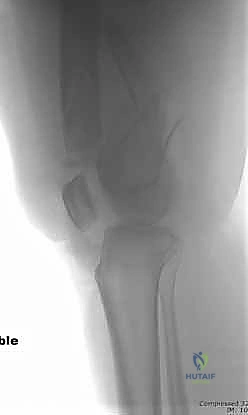

- الأشعة السينية (X-Rays): أخذ صور من زوايا متعددة (أمامي خلفي، وجانبي) لتحديد موقع الكسر ونوعه.

- الأشعة المقطعية (CT Scan): وهي ضرورية جداً في كسور عظم الفخذ البعيدة، خاصة إذا كان الكسر يمتد إلى داخل مفصل الركبة (Intra-articular fractures). تساعد الأشعة المقطعية الدكتور هطيف على بناء نموذج ثلاثي الأبعاد للكسر، مما يسهل التخطيط الجراحي وتحديد أماكن وضع المسامير بدقة.